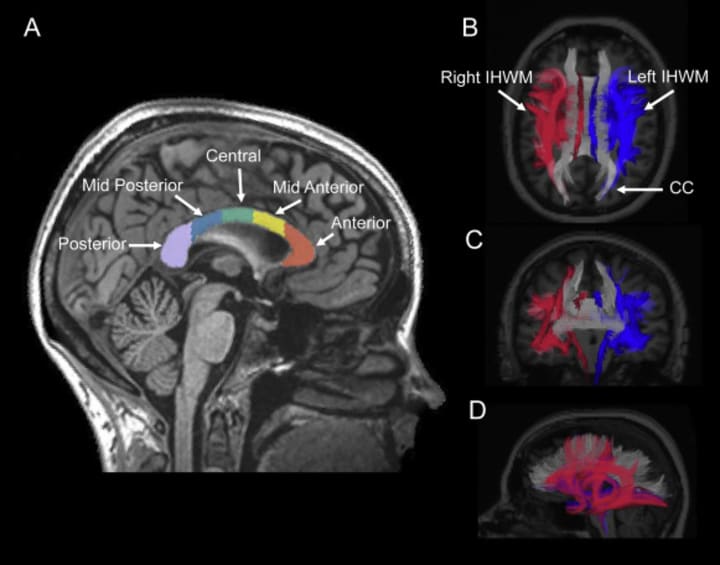

Again brain imaging have shown that the Corpus Callosum is the physical bridge between the hemispheres. In musicians, this part of the brain is larger in size and activity. This allows the flow of messages faster and through more diverse routes. This gives musician’s better ways to solve problems more effectively in both academic and social settings. All this just because making music involves crafting and displaying a vast array of emotions, music goes beyond playing the right notes and the right time.